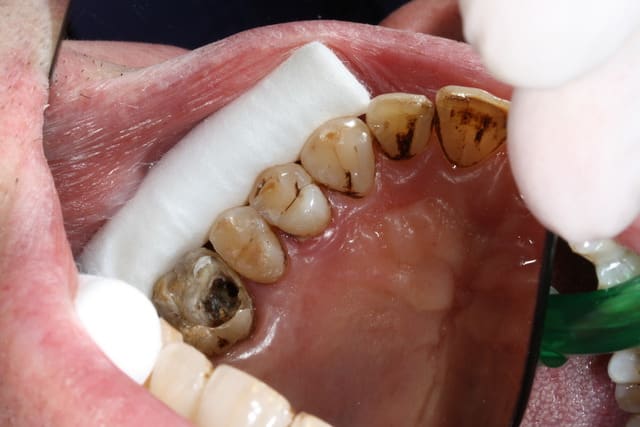

Voici le résultat d'une 3ème séance de recherche du MV 2 le vague à l'âme expliquant l'absence de digue , et mv 2 que j'aurai nommé le CCE pour casse couille endodontique mais n'étant pas endo exclusif je reste courtois avec cette désespérance souvent absente radiologiquement après obturation et dont le trajet incertain me laisse rêveur , quand à la guérison de l'image en mésial prions pour que Saint NaOCl et Saint EDTA veillent sur nous .

Et la paro partout, c'est à cause des tiges d'argent ?

Je salue ta conscience professionnelle, voire l'acharnement, je n'aurais probablement pas eu le courage d'une 3ème séance pour le mv2. D'ailleurs, je trouve que pour les reprises le mv2 me donne très souvent envie d'hurler, malgré l'attirail digue/loupes qui va bien. Sur des endos 1ère intention, je me sens plus attirée par ce foutu canal.

@Machu : oui, mais sur des dents sur lesquelless on laisse rentrer de nouveaux microorganismes (pas de digue, erreurs d'asepsie durant le retraitement, temporisation cavit/irm trop longue, scellement d'inlay-core sans désinfection préalable de la dent et de l'IC, IC mal ajusté, couronne mal ajustée ... sinon, sans une de ces erreurs, la lésion qui apparait serait de toute façon apparue.